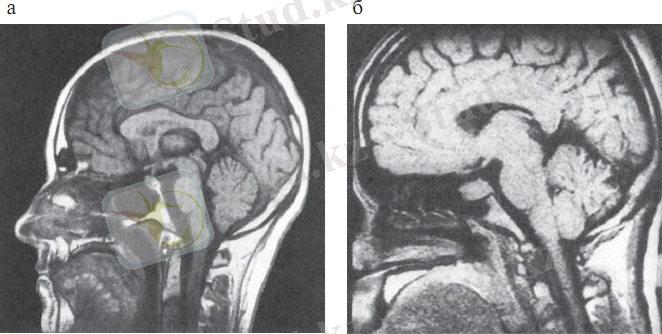

Гипофиз бен гипоталамусты визуализациялау әдісі ретінде, сонымен қатар гипоталамус-гипофизарлы аймақтағы түзілістердің топикалық диагностикасы мақсатында МРТ қолданылады (2. 4сурет) . МРТ гипофизде дамыған азғантай өзгерістердің өзін, ісіктердің, кисталардың, қан құйылулардың кистозды компоненттерін анықтауға мүмкіндік береді. МРТ-да сүйек тіндері мен түрлі тұздардың шөгуі анықталмайды.

Сурет 2. 4 . Гипоталамус-гипофиз аймағының магнитті-резонансты томографиясы

а - қалыпты жағдайда (сагиттальды проекция) ;

б - гипофиз макроаденомасы (сагиттальды проекция)

Контрасты заттарды қолдану МРТ-ның диагностикалық мүмкіндіктерін арттырады. МРТ-ның негізгі артықшылығы- сәулелік жүктеменің болмауы, яғни науқасты бірнеше рет динамикалық бақылау мүмкіндігінің болуында.